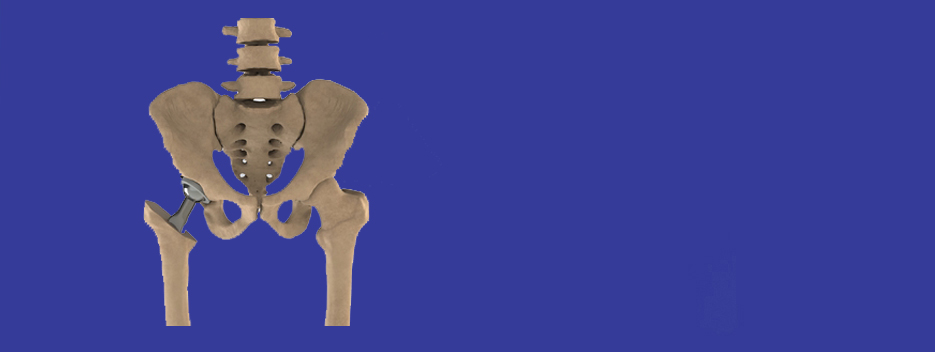

READ MOREDrive patient specific healthcare - Design new implants, stents and fixation plates that exactly match and fit patient anatomy, engineers and scientists need robust and reliable tools to help them efficiently and accurately convert patients scans data (CT/MRI) into computer models. These models need to be simulated/tested before final 3D print/manufacturing.

VOLMO uses its proprietary software ImageSim to design customised implants